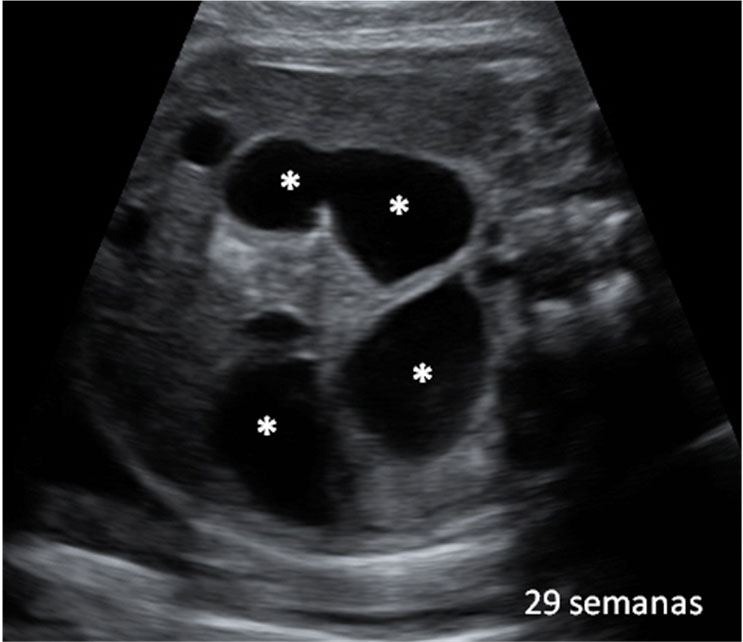

En la semana 20 de gestación el feto aún tiene mucho espacio para poder moverse. La embarazada notará esos movimientos, que se observan en la ecografía en 4D. Son las clásicas "pataditas" que nota la madre dentro del útero.